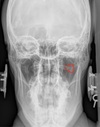

APOM ANATOMICAL LANDMARKS

maxillary sinus

29

frontal sinus

30

nasal aperature

31

nasal spine + septum

32

lower teeth

33

upper teeth

34

mandible

35

jugular process

36

A-P open mouth

rim of foramen magnum

37

anterior arch c1

38

posterior arch c1

39

A to P open mouth

lateral mass of c1

40

transverse process c1

41

medial inferior tip of occipital condyles

42

mastoid air cells

43

A-P open mouth view

pedicle shadow c2

44

spinous process c2

45

eop-iop

46

atlantal-axial joint space

47

vertebral bodies c2-c7

48

inferior articular surface c1

49

superior articular surface c1

50

A-P cervical

uncinate process of cervical vertebra

51

occipital-atlantal joint space

52

odontoid process